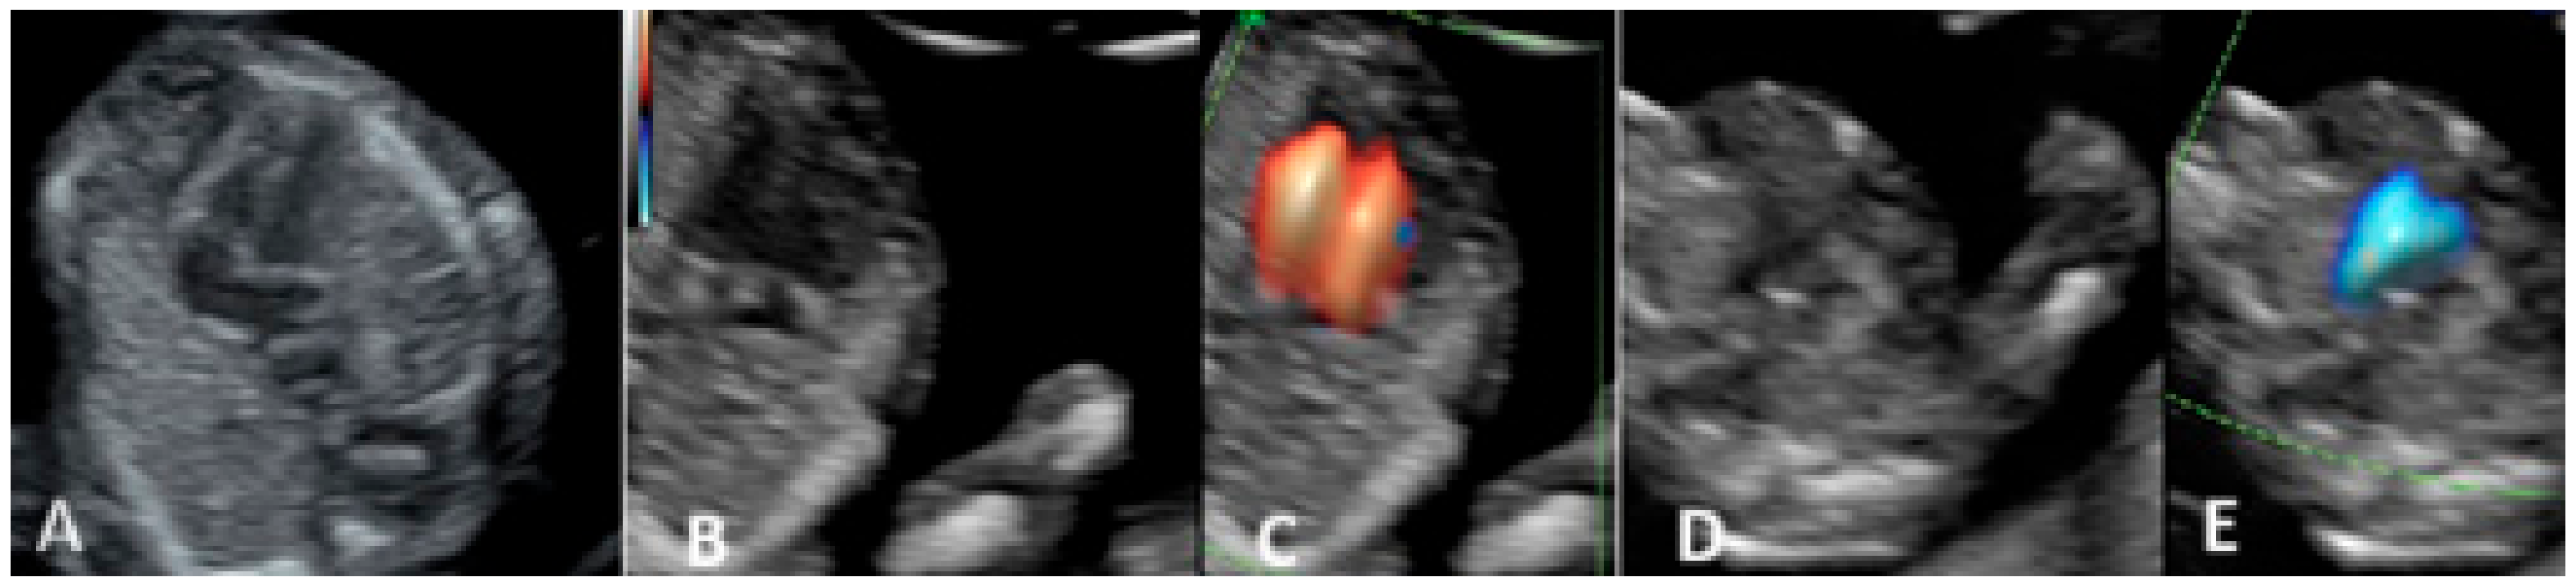

3.1. First-Trimester Evaluation

- Herghelegiu, C.G.; Panaitescu, A.M.; Duta, S.; Vayna, A.M.; Ciobanu, A.M.; Bulescu, C.; Ioan, R.G.; Neacsu, A.; Gica, N.; Veduta, A. Ultrasound Patterns in the First Trimester Diagnosis of Congenital Heart Disease. J. Clin. Med. 2021, 10, 3206. [Google Scholar] [CrossRef] [PubMed]